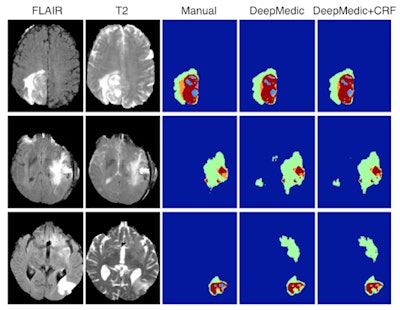

Machine learning is used in a wide range of projects at Imperial College and these are helping to reveal how the technology can unlock patterns and subtle signs of disease often difficult for humans to spot, due to the complex nature of the imaging data. Their machine-learning algorithms automatically detect and quantify brain lesions and can analyze the structure and function of the heart. Other projects include whole-body imaging, where algorithms are helping radiologists find abnormal and suspicious regions.

Glocker presented a number of example applications where his group successfully applied a form of machine learning called deep learning. He included results from brain, cardiac, and whole-body imaging, where the group's algorithms were close to the accuracy of a human expert.